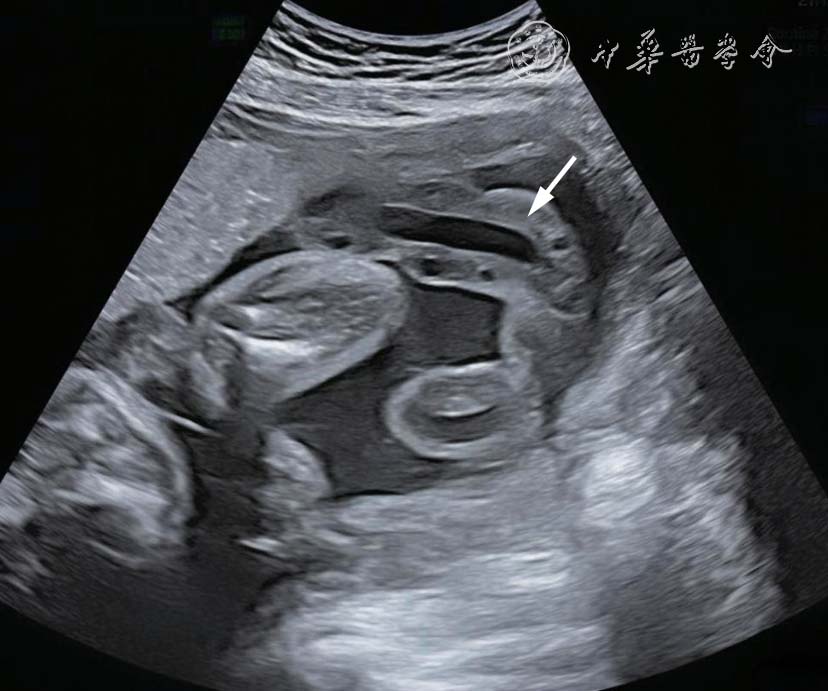

图2 双胎贫血-红细胞增多序列征胎儿孕22+5 周产前超声图像可见供血儿脐带入口附近胎盘回声增强、增厚,受血儿脐带入口附近胎盘回声减低、较供血儿侧薄

26 例TAPS 均在中晚孕期(孕17+1~34+6 周)超声检查中发现,其中Ⅰ期11 例,Ⅱ期3 例,Ⅲ期3 例,Ⅳ期9 例,Ⅴ期0 例。共有的超声特征为:(1)供血儿MCA-PSV 增高(>1.5 MoM),受血儿MCA-PSV 降低(<1.0 MoM)( 图1);(2)“黑白”胎盘:供血儿脐带入口附近胎盘回声增强、增厚,受血儿脐带入口附近胎盘回声减低、较供血儿侧薄(图2)。其他超声特征包括:(1)24例(92%)受血儿肝呈“星空征”(图3);(2)4例(15%)供血儿肠管回声增强(图4);(3)22例(85%)心脏异常,包括心胸比增大、房室瓣反流、房室瓣频谱呈单峰、心肌增厚等征象(图5a、5b);(4)18 例(69%)多普勒血流异常,包括脐动脉、脐静脉、静脉导管A 波异常等;(5)9 例(34%)胎儿水肿,包括皮肤水肿、胸腹腔积液、心包积液;(6)15 例(57%)羊水量不均衡;(7)19 例(73%)脐带异常,包括脐带水肿、脐带插入点异常(图6);(8)15 例(57%)合并双胎选择性宫内生长受限(selective intrauterine growth restriction,sIUGR)、TTTS(表1)。对供血儿及受血儿其他超声特征进行统计分析发现,受血儿肝“星空征”、脐带水肿,供血儿肠道回声增强、胎儿水肿、心胸比增大特征比较,差异有统计学意义(P<0.05,表2)。